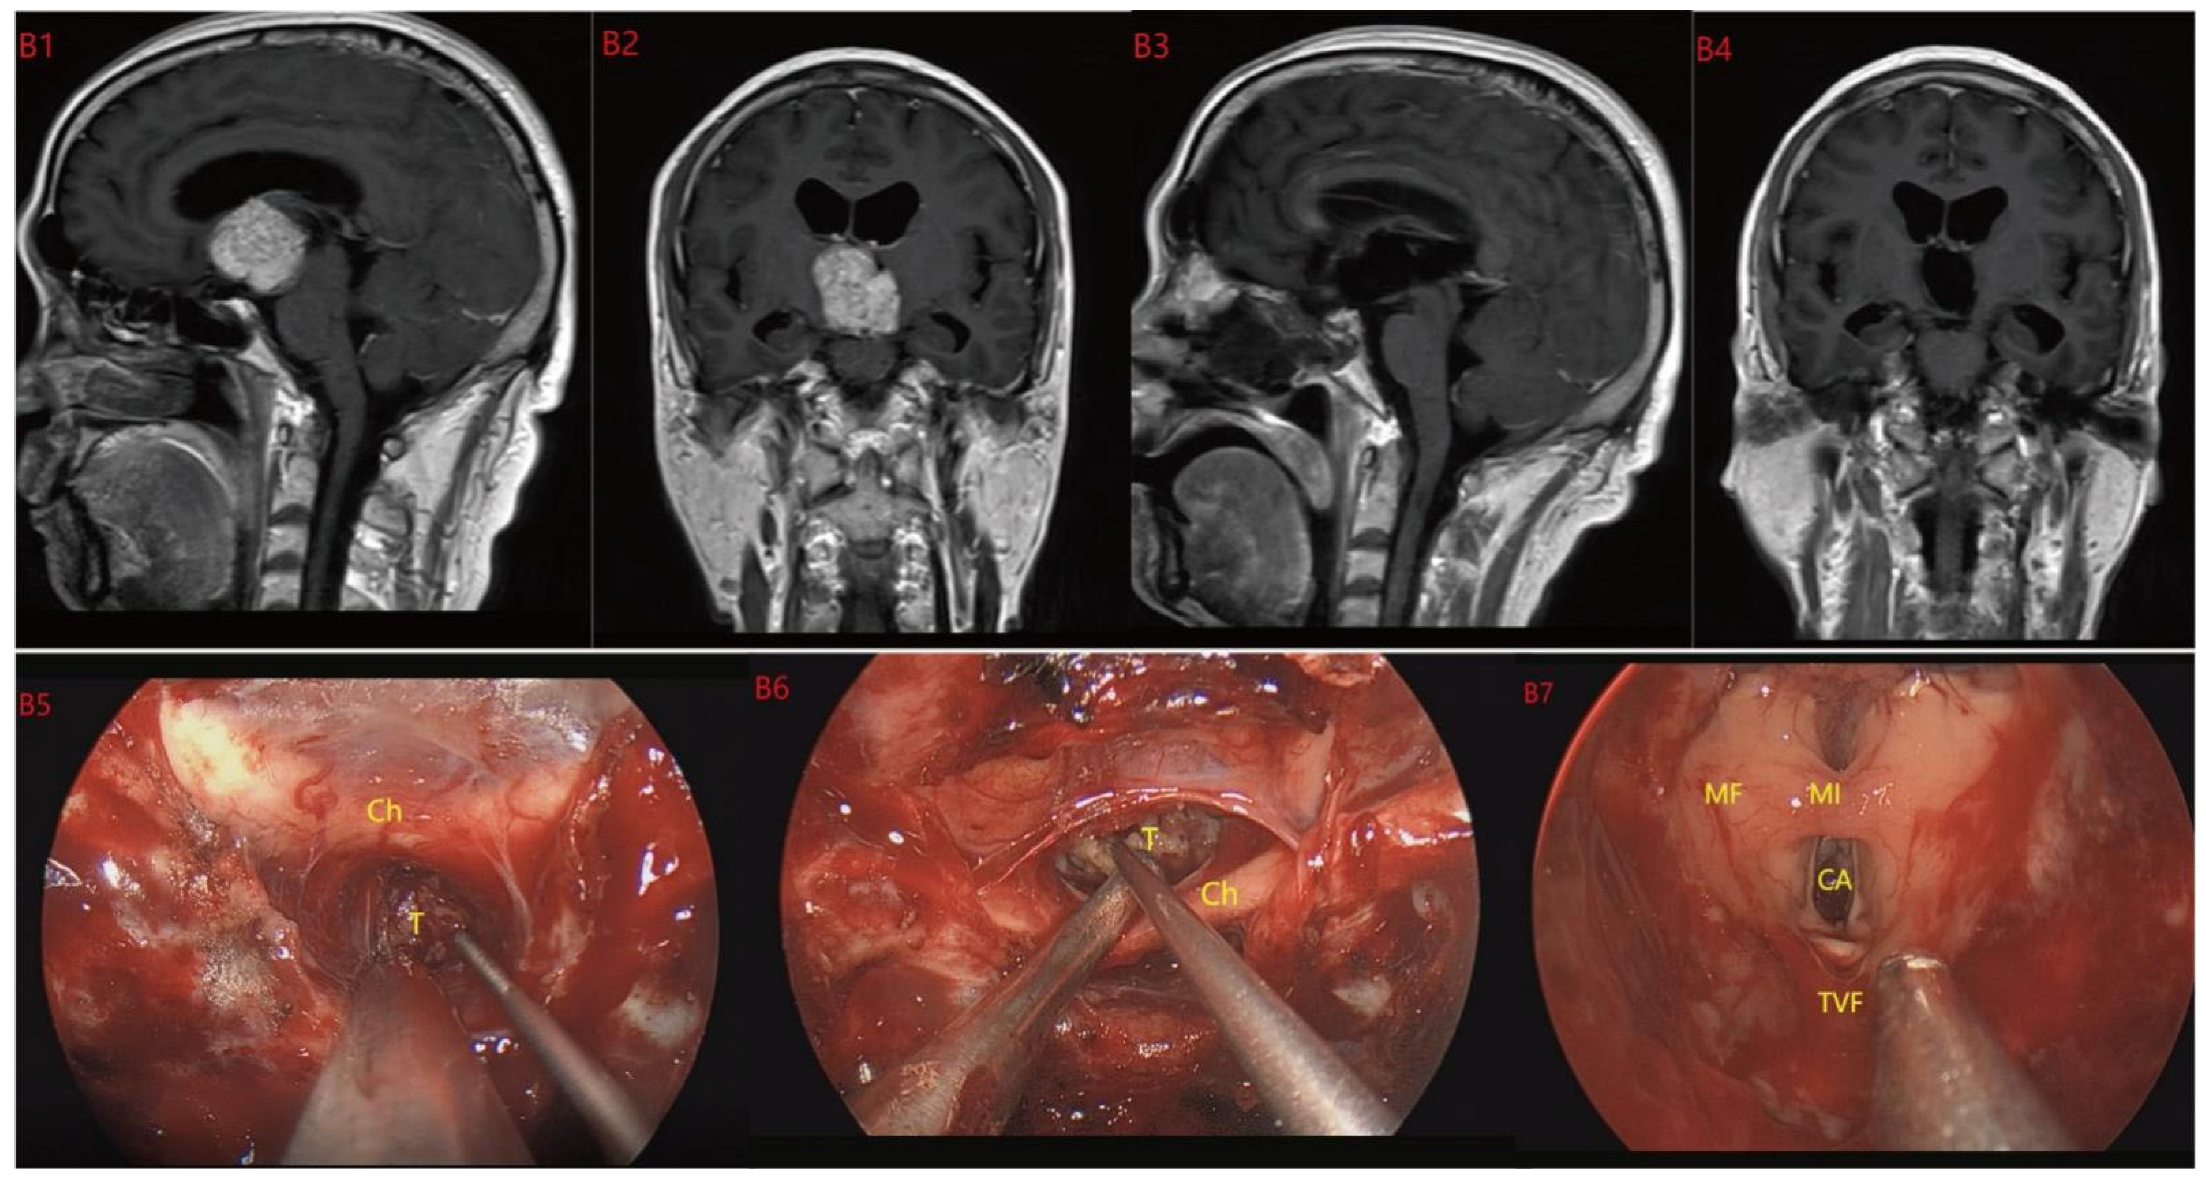

Based on MRI data and intraoperative findings from EEA, we classified PCPs into three types: (1) Type I: Suprasellar/intra-suprasellar (3V floor intact) type: most tumors originate from the segments of the pituitary stalk between diaphragma and infundibulum, as shown in Figure 1. (2) Type II: Suprasellar/intra-suprasellar (3V floor invasive) type: most of the tumors originate from pituitary stalk (PS), or infundibulum and median eminence (ME); the interface between tumor and 3V floor is not clear or has disappeared, and the tumor infiltrates into the bottom of the third ventricle, as shown in Figure 2 and Figure 3. (3) Type III: Intra-third ventricle type; most of the tumors originate from the infundibulum and ME, the tumor grows strictly inside the third ventricle, the 3V floor is intact and covered with arachnoid membrane, as shown in Figure 4 and Figure 5.

Figure 5.

Case 5 Type III: the tumor grows strictly inside the third ventricle. (B1,B2) The TCPCA AND TLTA was used; the pituitary stalk could not be seen during the surgery (B5–B7). The TVF was intact. The tumor was finally totally resection (B3,B4). Optic chiasm (Ch), foramen of Monroe (MF), massa intermedia (MI), cerebral aqueduct (CA), tumor (T).